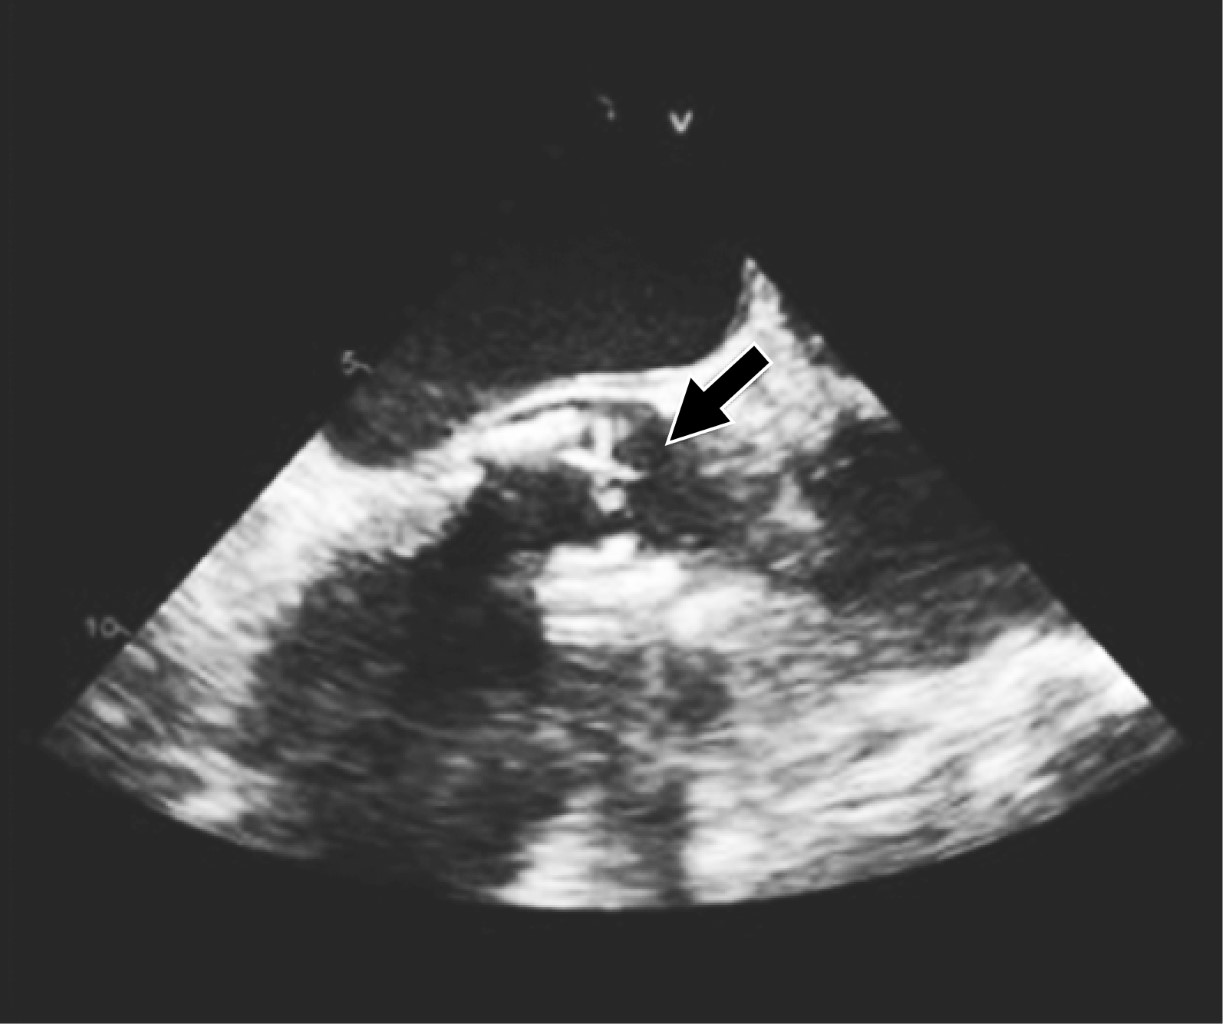

La endocarditis infecciosa en válvulas nativas o en válvulas reemplazadas quirúrgicamente ha sido ampliamente descrita en la literatura; sin embargo, respecto a la endocarditis infecciosa en válvulas bioprotésicas transcatéter, aún se encuentra en un proceso continuo de investigación. Presentamos el caso de una paciente de 66 años con diagnóstico de endocarditis infecciosa temprana de válvula protésica aórtica percutánea SAPIEN 3, quien tuvo una evolución clínica y desenlace favorable con tratamiento médico conservador basado en antibióticos, a pesar de que la incidencia de mortalidad intrahospitalaria a causa de EI-TAVR, representa más de 40%. Reportar nuevos casos clínicos con sus diferentes características, sus tratamientos y resultados obtenidos, se considera de suma importancia para apoyar a un mejor diagnóstico y tratamiento médico en futuros pacientes.

Figura 3